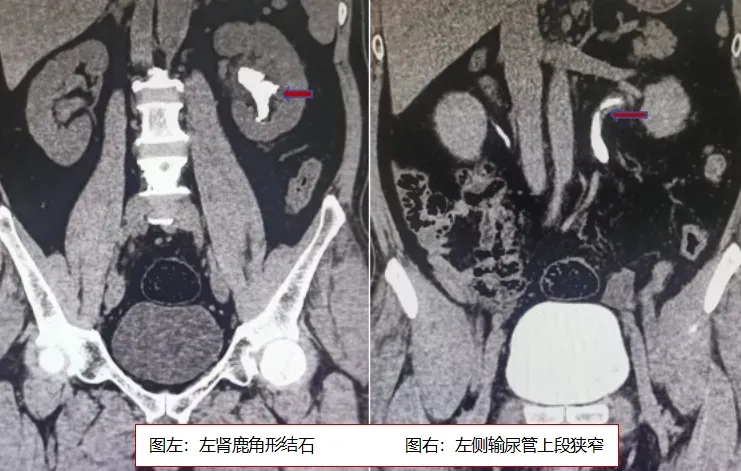

患者因长期熬夜加班、饮食不规律,日常疏于健康管理,2周前突然出现尿频、尿急、血尿等不适症状。听闻我院泌尿外科技术精湛、服务贴心,他专程前来就诊。入院后,经CT检查明确诊断:患者左侧肾盂肾盏多发结石,结石直径超过4cm,呈典型的鹿角形结构,且已深入突入上、中、下三个肾盏——这属于泌尿外科临床中极具挑战性的复杂性肾结石。此类结石不仅体积大、位置分散,还可能损伤肾实质,若不及时治疗,将严重影响肾功能。

手术过程中,团队遭遇了“输尿管狭窄导致器械通行困难”“肾内操作空间狭小”“部分肾盏狭长难以抵达” 等多重挑战。但凭借丰富的临床经验和默契的多学科协作,医护人员稳扎稳打:先通过输尿管扩张技术解决狭窄问题,再调整软镜角度配合可弯曲吸引鞘,逐一清除各个肾盏内的结石,最终顺利完成碎石与清石操作。术后当天患者即可进食、活动,无出血、发热、腰痛等不适。复查腹部X线片显示:左肾输尿管无明显结石影。患者恢复良好,术后第3日顺利出院。(康文玉)